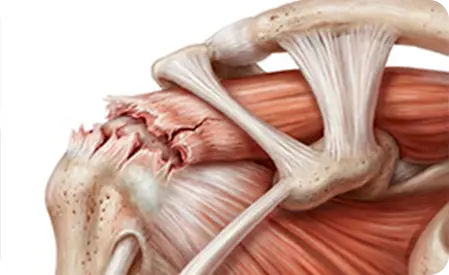

O manguito rotador é um conjunto de músculos e tendões que envolve a articulação do ombro. Ele funciona como um sistema de estabilização que mantém o braço conectado à articulação do ombro durante os movimentos.

O manguito rotador é composto por quatro músculos principais:

- Supraespinhal

- Infraespinhal

- Subescapular

- Redondo menor

Esses músculos trabalham juntos para permitir que o braço execute movimentos de rotação, elevação e estabilização.

Sem o funcionamento adequado do manguito rotador, atividades simples do dia a dia podem se tornar difíceis ou dolorosas.

Por isso, essa estrutura é extremamente importante para a mobilidade e estabilidade do ombro.